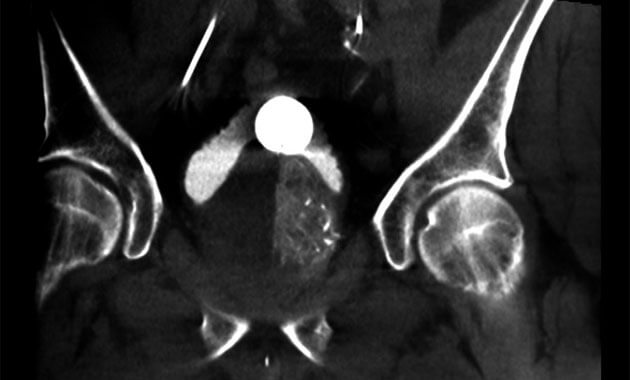

Prostate enlargement, also known as benign prostatic hyperplasia (BPH), is a common condition in older men that causes symptoms such as poor urinary flow, frequent urination during the day and night, incomplete bladder emptying, and sudden urge to urinate. This disease may be treated with oral medications, but not all patients have relief of their symptoms with medications alone. In patients with severe symptoms, a urologist may recommend a surgical procedure, such as transurethral resection of the prostate (TURP).

Prostate artery embolization (PAE) is a minimally invasive alternative to surgical procedures like TURP. PAE shrinks the prostate by treating its blood vessels. It is performed by an interventional radiologist through a small incision in the upper thigh.

Dr. Ryan Kohlbrenner and his team use specialized techniques to perform prostate artery embolization (PAE), a procedure being increasingly used in the United States to treat prostate gland enlargement and its associated urinary symptoms. Through a small incision in the upper thigh, access to the prostate's blood vessels is gained, and small particles are injected to slow the blood flow to the gland. In the weeks and months following PAE, the prostate relaxes and shrinks, resulting in symptom relief for most men. Although conventional prostate surgery can be associated with complications like impotence and incontinence, PAE is a minimally-invasive alternative that is not known to cause these issues. We are happy to now offer this procedure to UCSF patients.